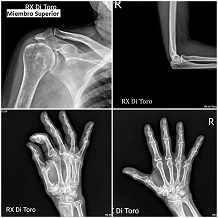

Utilizamos sensores Flat Panel, que nos permiten acortar al Máximo el tiempo de exposición (Dosis de Radiación) y obtener la adquisición inmediata de las imágenes.